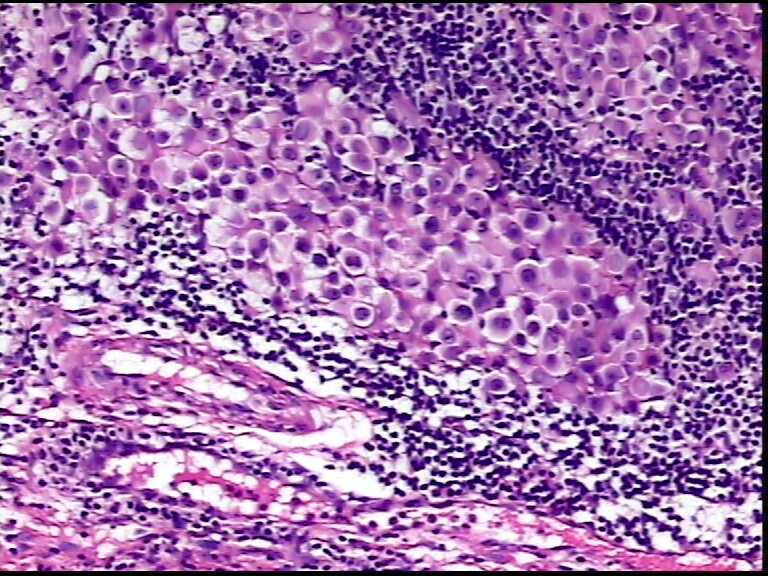

患者男性,34岁,临床没给提供,该患者梅毒阳性

• 请各位老师会诊一下 颌下淋巴结图3

图3

颌下淋巴结肿大,送检肿物直径2.5cm,切面灰粉色,质地嫩,先做了个LCA瘤细胞阴性

淋巴结内见大量宽而嗜酸性胞浆的肿瘤细胞,瘤细胞核大,偏心分布,核仁明显,成上皮样表现,部分似有腺泡样排列,符合淋巴结转移性恶性肿瘤,首先除外转移癌,恶性黑色素瘤,继而除外浆细胞瘤(岁数不太符合),横纹肌肿瘤等。

这个地方类似这样的病变太多,结合患者年龄,建议先考虑嗜酸细胞性黏液表皮样癌和肌上皮瘤,然后再考虑恶黑或癌

淋巴结内见大量宽而嗜酸性胞浆的肿瘤细胞,瘤细胞核大,偏心分布,核仁明显,成上皮样表现,部分似有腺泡样排列,符合淋巴结转移性恶性肿瘤,首先除外转移癌,恶性黑色素瘤,继而除外浆细胞瘤(岁数不太符合),横纹肌肿瘤等。同意楼上的观点。